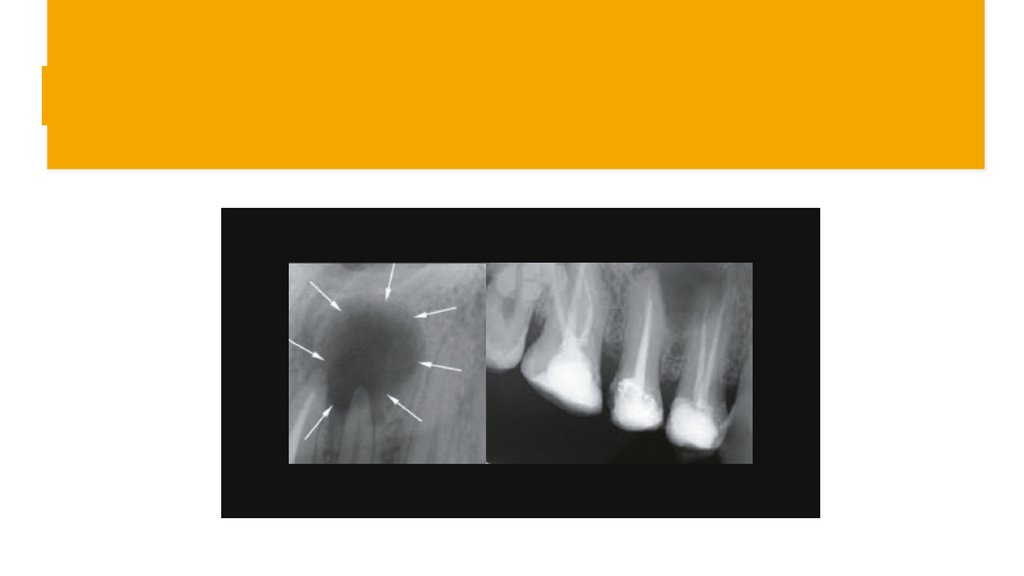

Радикулярлы киста дегеніміз не?

Капсула мен сұйықтықтан тұратын

ісік тәрізді құрылым